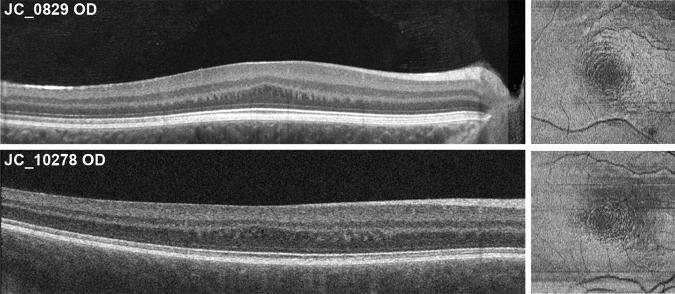

Directional optical coherence tomography (D-OCT) allows the visualization of the Henle fiber layer (HFL) in vivo. Here, we used D-OCT to characterize the HFL and outer nuclear layer (ONL) in albinism and examine the relationship between true foveal ONL and peak cone density.

Horizontal D-OCT B-scans were acquired, registered, and averaged for 12 subjects with oculocutaneous albinism and 26 control subjects. Averaged images were manually segmented to extract HFL and ONL thickness. Adaptive optics scanning light ophthalmoscopy was used to acquire images of the foveal cone mosaic in 10 subjects with albinism, from which peak cone density was assessed.

Across the foveal region, the HFL topography was different between subjects with albinism and normal controls. In particular, foveal HFL thickness was thicker in albinism than in normal controls (P < 0.0001), whereas foveal ONL thickness was thinner in albinism than in normal controls (P < 0.0001). The total HFL and ONL thickness was not significantly different between albinism and controls (P = 0.3169). Foveal ONL thickness was positively correlated with peak cone density in subjects with albinism (r = 0.8061, P = 0.0072).

Foveal HFL and ONL topography are significantly altered in albinism relative to normal controls. Our data suggest that increased foveal cone packing drives the formation of Henle fibers, more so than the lateral displacement of inner retinal neurons (which is reduced in albinism). The ability to quantify foveal ONL and HFL may help further stratify grading schemes used to assess foveal hypoplasia.